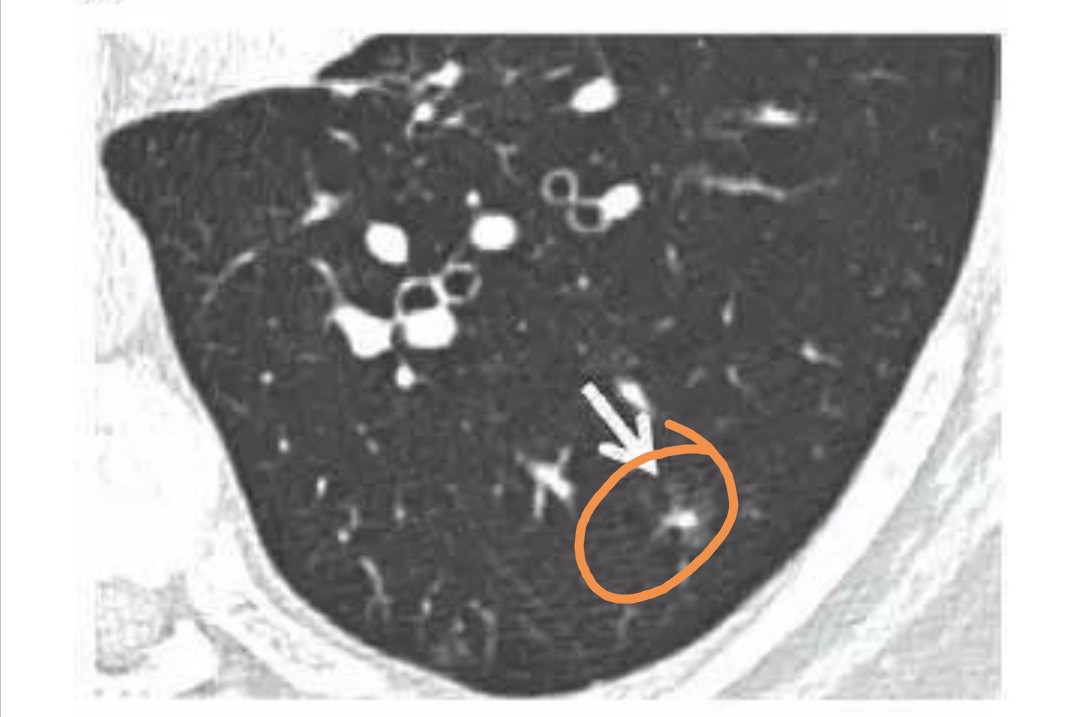

密度不均匀的部分实性结节,实性成分超过50%,提示恶性可能大。实性成分越多,发生侵袭和转移的可能性越大。

- 因此,对于6 mm 及以上实性成分的部分实性结节,应考虑 3~6 个月行CT扫描随访来评估结节。对于具有特别可疑形态(即分叶或囊性成分)、连续生长或实性成分大于8毫米的部分实性结节,建议采用 PET-CT、活检或切除术。

部分实性结节